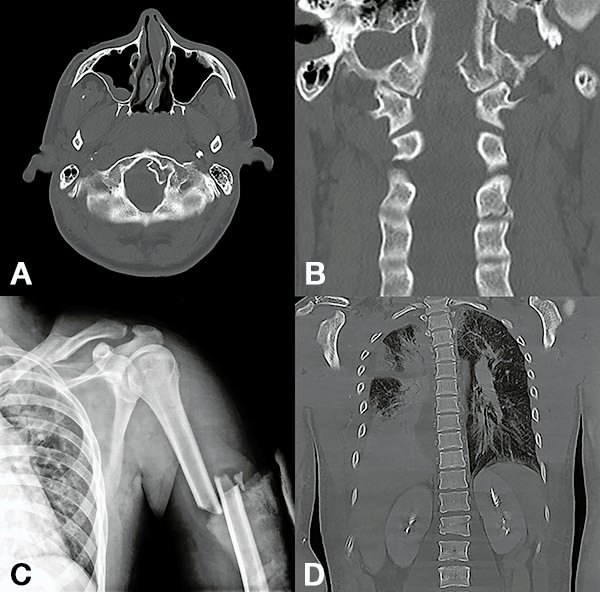

Figura 4:

Caso 8. Hombre de 52 años, accidente vehicular de alta energía cinética. Fractura cerrada de antebrazo, síndrome de distrés respiratorio, hemotórax bilateral, hematocrito en descenso. Se diagnostico una fractura A4 de T8 con mínimo compromiso del canal espinal, posición en cifosis y hemotórax bilateral a predominio izquierdo.

Figura 5:

Caso 8. Se realizó una estabilización percutánea T6-T10. El paciente retornó a UTI, para estabilizar su cuadro respiratorio y hemodinámico.

Figura 6:

Caso 8. A la semana de la primer cirugía el paciente se encontraba en condiciones y se realizó la corpectomía por via lateral MIS.